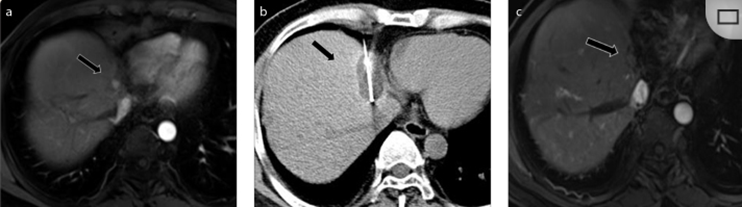

( a ) 軸向 MRI 和 ( b ) 軸向 CT 顯示肝S8段有一個16mm的病灶,鄰近肝緣。( c )冷凍消融期間CT顯示放置了2個冷凍探針,低密度冰球包圍病灶。(d)術后1個月隨訪 CT顯示冰球對應的壞死區域,未見復發。(f)與基線影像(g)相比,12個月后的FDG-PET/CT顯示未見FDG攝取。

(a)軸向CT顯示病變位置毗鄰心臟和上腔靜脈(黑色箭頭)。1個月后的軸向(e)和冠狀位(f)增強CT掃描顯示低密度區域,由于肉芽組織反應引起的邊緣增強。

技術成功100%,92% 的病灶中觀察到腫瘤完全消融。16 名患者 (33%) 出現局部復發。10 名患者 (20%) 因局部復發或腫瘤消融不完全而接受二次冷凍消融術。

7名患者出現輕微并發癥,未發現膿腫形成、膽漏、膽汁瘤或血液學變化。冷凍消融可安全、有效治療毗鄰重要臟器的原發性肝臟腫瘤和肝轉移瘤患者,有效控制腫瘤局部進展,使患者生存獲益。我國作為肝癌大國,對于肝癌的治療一直給予高度重視?;趯<夜沧R和相關文獻研究結果顯示,冷凍消融技術具有高效、低成本、創傷小、適應證廣、并發癥相對較少等優點,可有效延長患者生存期、提高生活質量、降低患者經濟負擔。因此,冷凍消融技術在肝癌的應用中有著極高的潛力和廣泛的發展空間。